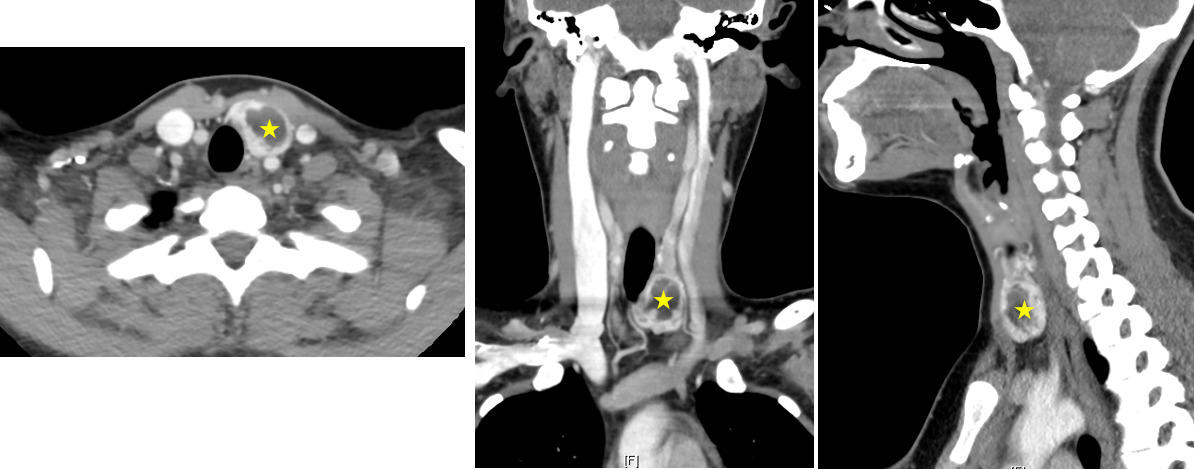

A neck computed tomography (CT) scan with contrast showed an enlarged left thyroid gland with a heterogeneous hypodense nodule measuring 1.9 x 1.1 x 2.3 cm. The left thyroid lobe was seen to be abutting the anterior upper esophageal wall without significant mass effect on the trachea, esophagus or vascular structures of the neck (Figure 1). The patient also had a smaller, sub-centimeter hypodense nodule in the right thyroid lobe.